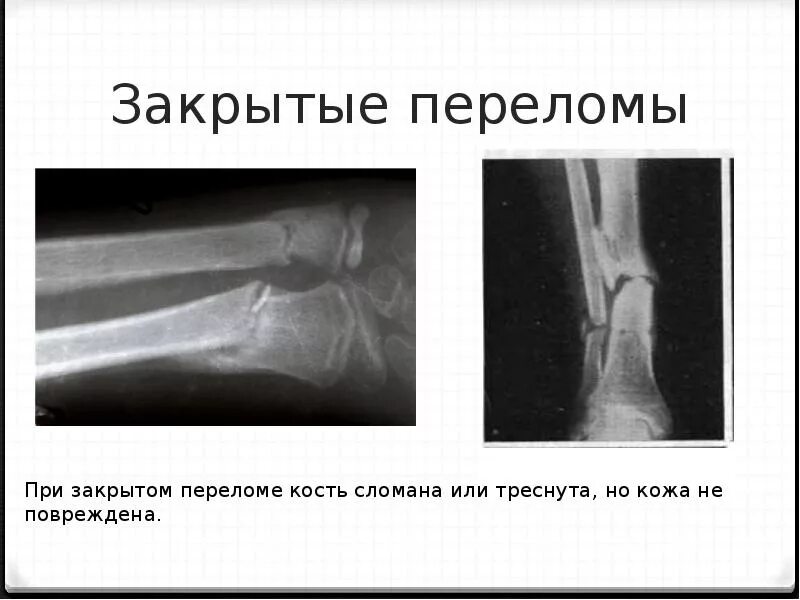

Открытые и закрытые вывихи